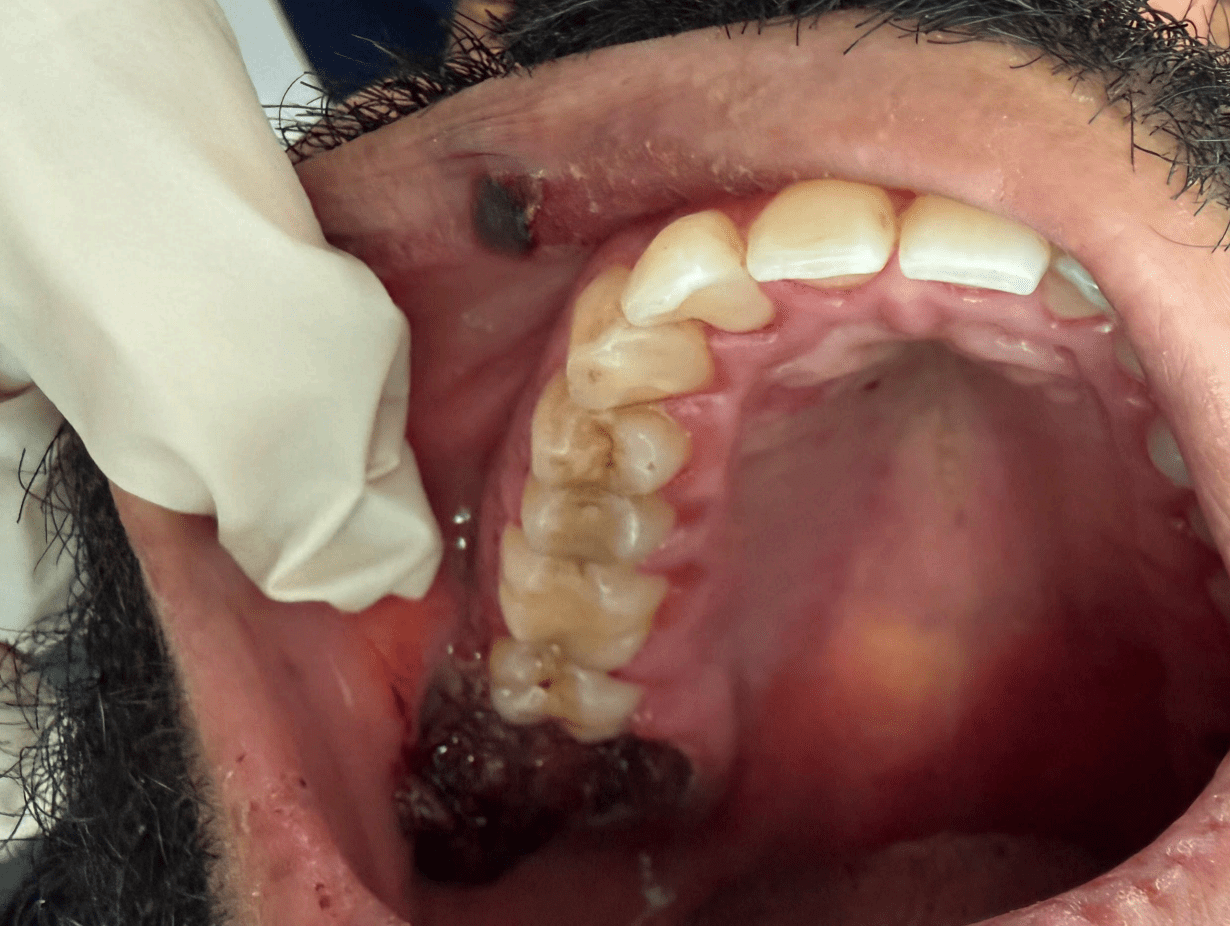

Over the following two weeks, the patient developed:

- Multiple liver clots at surgical sites

- Progressive edema and erythema of gingiva and extraction sites

- At one week: Ecchymosis and ulcerations were present intra and extraorally